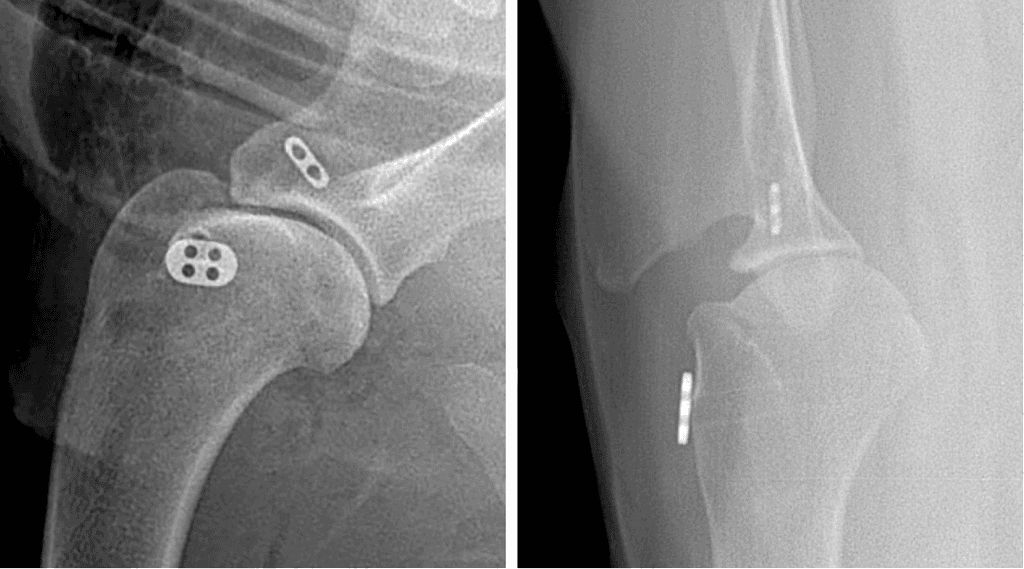

Shoulder Arthrodesis

In severe cases where the joint cannot be reconstructed or reconstruction fails, then a shoulder arthrodesis (fusion) may become necessary. The joint surfaces of the shoulder are removed then the shoulder completely fused used bone plates and screws. The stabilization will be protected by at least 6-8 weeks in a splinted bandage. X-rays are evaluated at 8 and 12 weeks to assess fusion then activity is slowly returned to normal.

Shoulder arthrodesis (fusion) effectively improves comfort and, in many cases, will improve function in the severely affected. The repair will be protected with splinted bandage for the first 8 weeks and exercise restricted for 12-16 weeks to allow adequate fusion. Once the splint is removed, rehabilitation can begin to train them how to move appropriately with the shoulder fusion. The biggest risks are implant infection (<5%) or implant failure (<1%) which can be limited with strict adherence to postoperative recommendations.